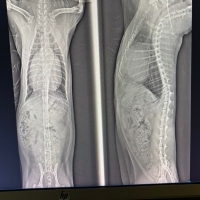

Merhaba, 3 yaş British kedime bugün ppdh teşhisi konuldu. Yani karaciğer olması gereken yerde değil kalbe yakın durumdaymış. Kesinlikle ameliyat olması gerekiyor dedi veteriner. Ameliyatla karaciğer doğru yerine konumlandırılacakmış. Daha önce böyle bir şey duyan yaşayan var mı riskleri olan bir operasyonmuş 😢 kalp konusunda uzman bir veteriner koydu bu teşhisi. Röntgen görüntüsünü ekliyorum